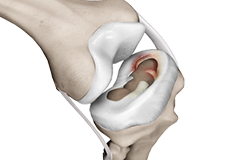

Articular Cartilage and Menisci of the Knee

Movement of the bones causes friction between the articulating surfaces. To reduce this friction, all articulating surfaces involved in the movement are covered with a white, shiny, slippery layer called articular cartilage. The articulating surface of the femoral condyles, tibial plateaus and the back of the patella are covered with this cartilage. The cartilage provides a smooth surface that facilitates easy movement.

Within the knee joint, between the femur and tibia, are two C-shaped cartilaginous structures called menisci. Menisci function to provide stability to the knee by spreading the weight of the upper body across the whole surface of the tibial plateau. The menisci help in load-bearing i.e. it prevents the weight from concentrating onto a small area, which could damage the articular cartilage. The menisci also act as a cushion between the femur and tibia by absorbing the shock produced by activities such as walking, running and jumping.